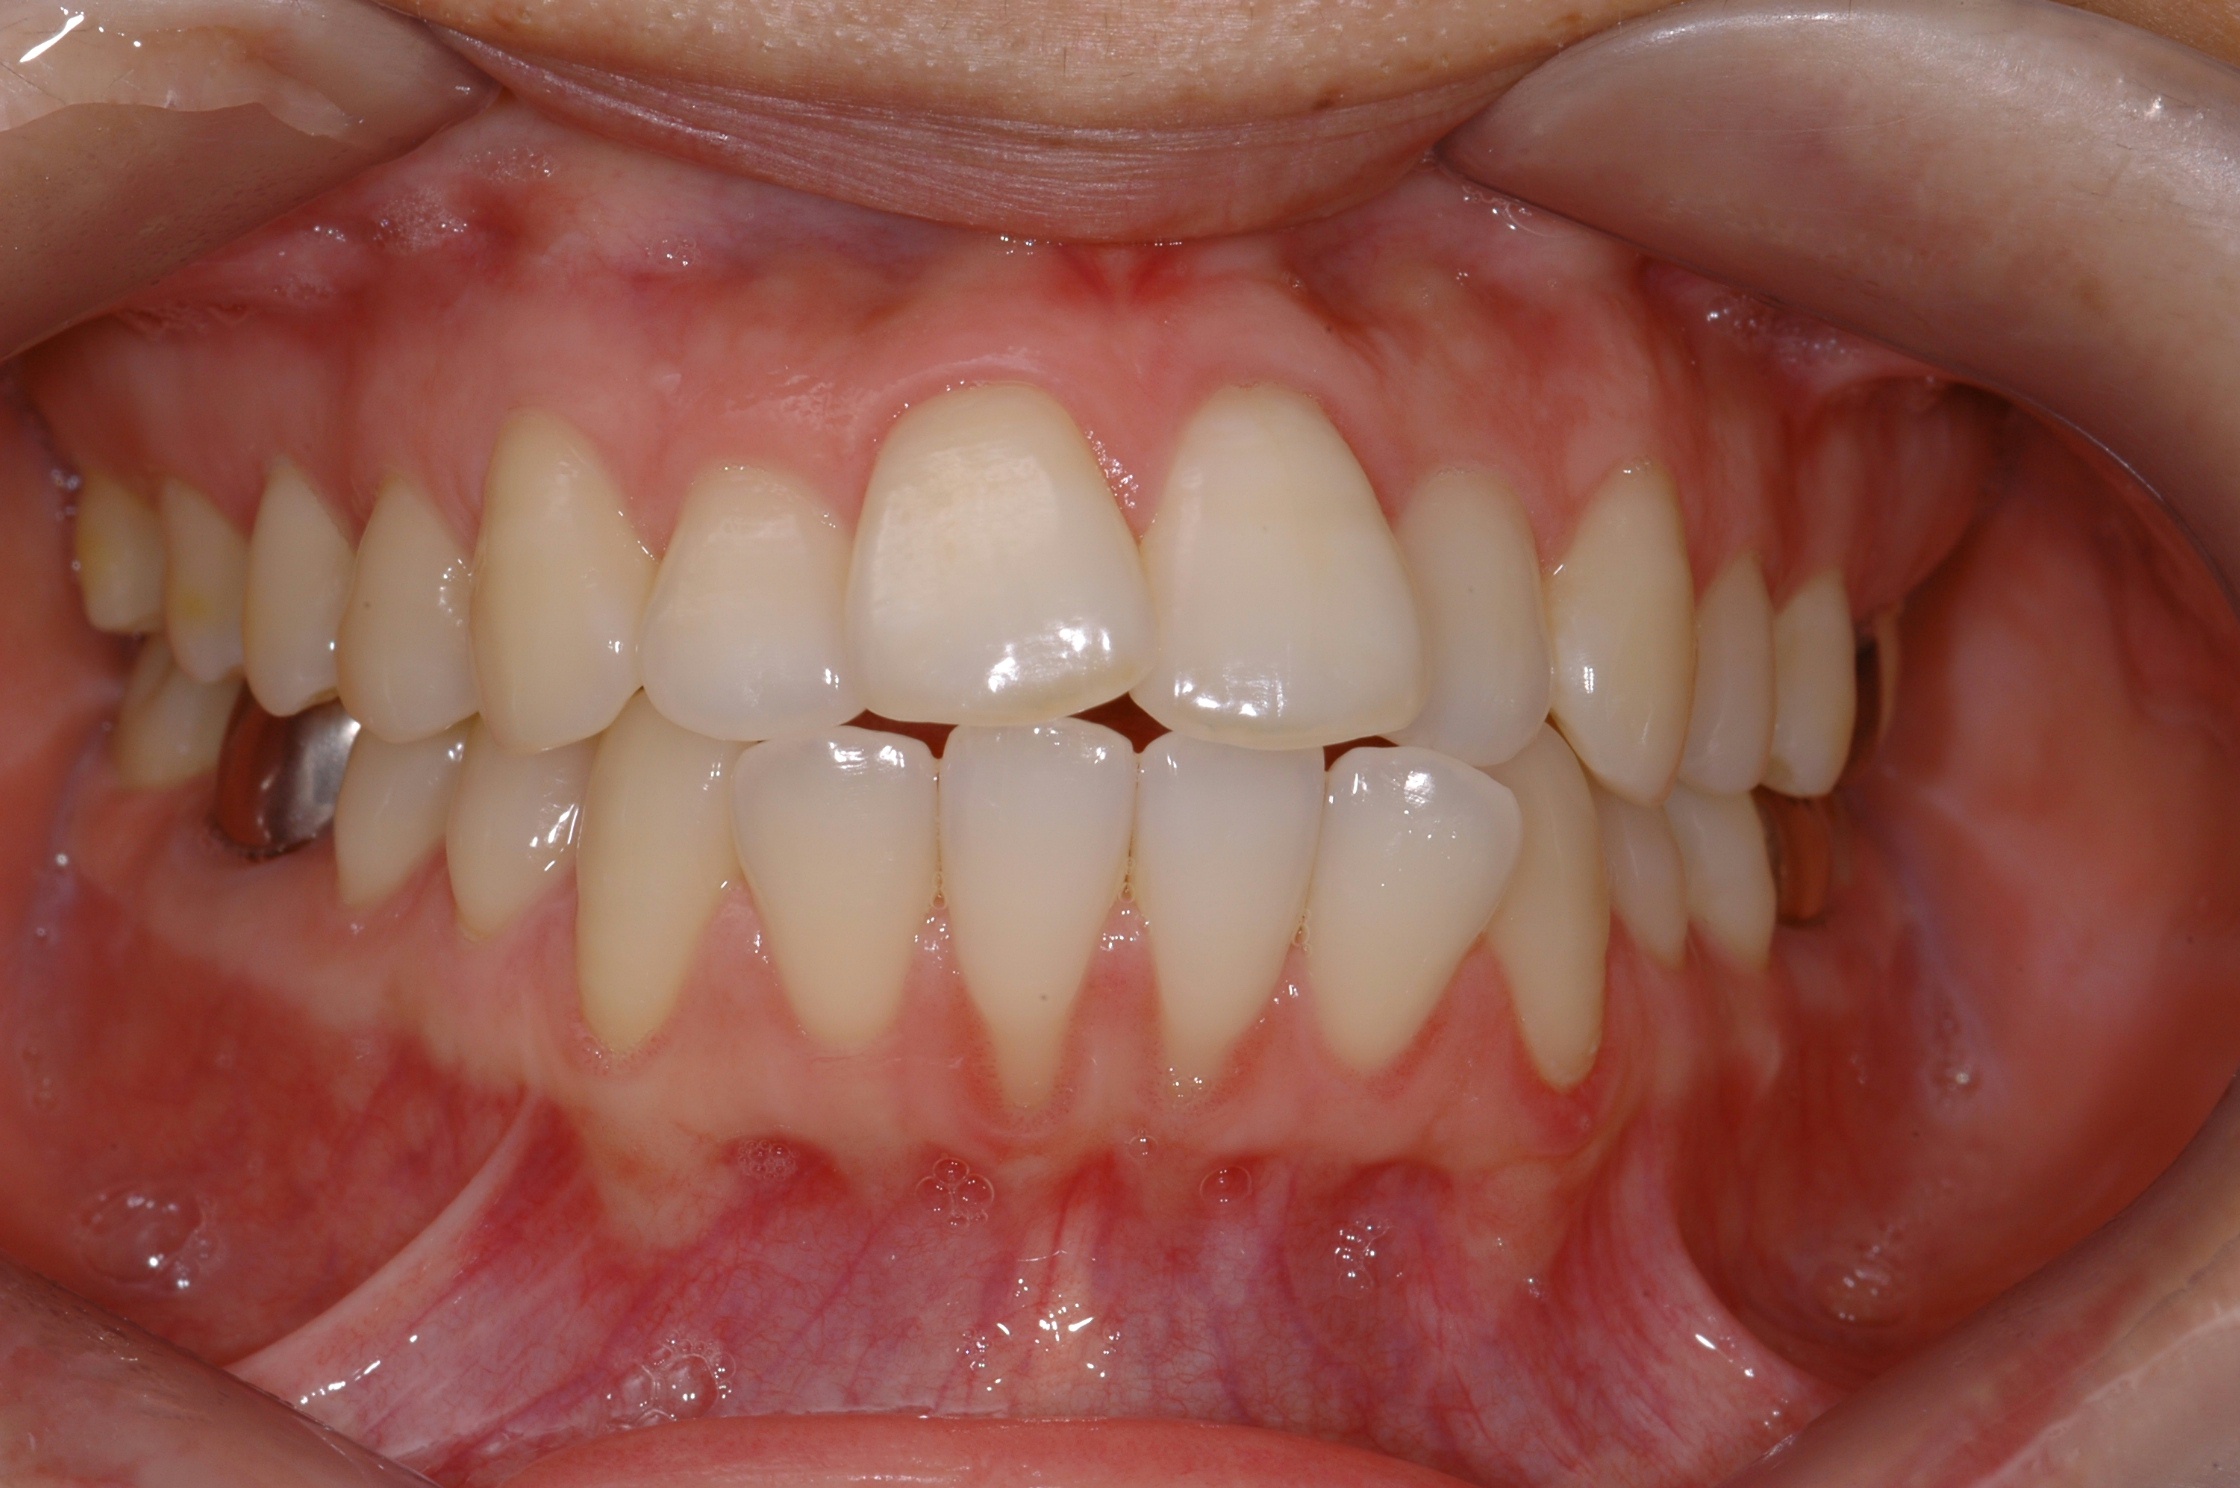

치료 후 사진입니다.